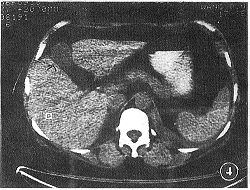

腹腔橫斷面(通過網膜孔)